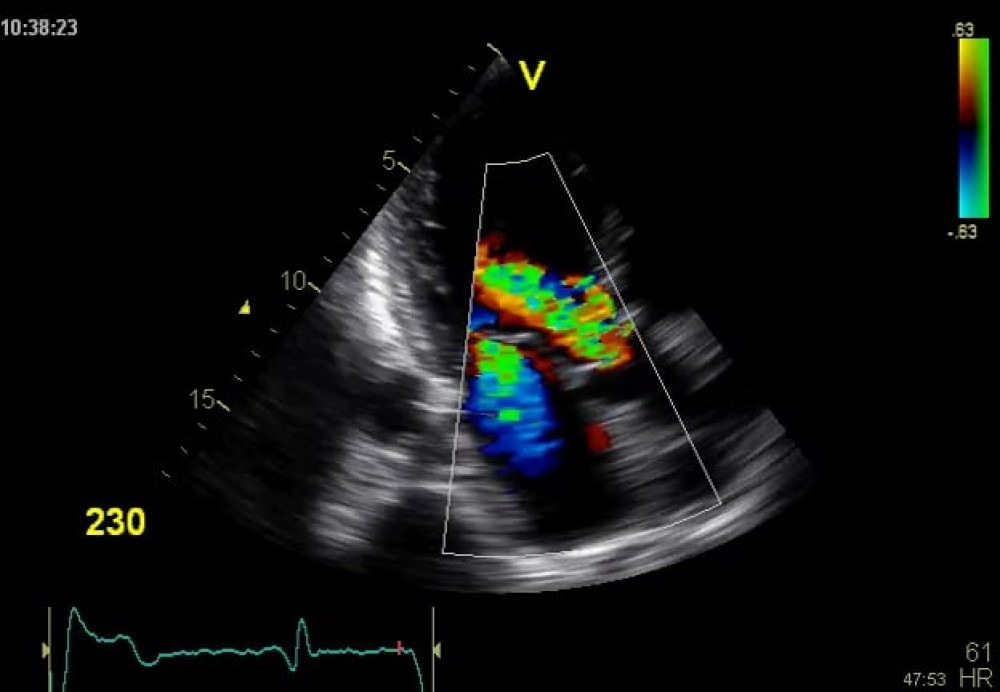

COLOR DOPPLER

The Color Doppler Ultrasound is a procedure in which high-frequency sound waves is used to estimate the blood flow through your arteries and veins that supply blood to your legs and arms. It is not as same as a regular ultrasound that uses sound waves to generate images but can’t show blood flow. This procedure is risk-free and pain-free.

The Color Doppler can also disclose the choked or reduced blood flow through narrowed areas in the arteries, which could ultimately lead to a stroke. This test provides all important information to your doctor regarding the flow of your blood through your major arteries and veins.